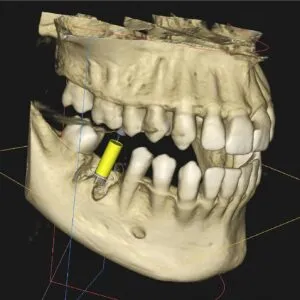

This type of imaging looks at interior structures of the mouth and jaw in 3-D. This type of imaging is used to find problems in the bones of the face such as cysts, tumors, and fractures. CT scans are also useful in implant work and more complex root canal treatments.